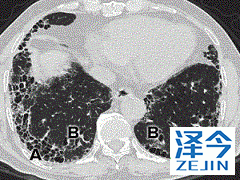

勃林格殷格翰的尼达尼布能够为IPF患者提供帮助 到目前为止,特发性肺纤维化的病因还没有明确,临床上也没有什么能够治愈的治疗方案,患者都在焦急的等待着能够有效的治疗方案,尼达尼布虽然不能够治愈患者,但是通过降低肺功能,能够为破坏性疾病的患者提供帮助与治疗的希望。

肺功能的下降,主要终点,通过强迫肺活量(FVC,以mL计)超过一年(年降低率)与安慰剂相比较。FVC是在完全吸入后可以强制呼出的空气量。

在研究中,实验发现尼达尼布是一种激酶抑制剂,可阻断与IPF有关的生长因子受体 - 包括血管内皮生长因子受体(VEGFR),成纤维细胞生长因子受体(FGFR)和血小板衍生生长因子受体(PDGFR)。尼达尼布批准是IPF的一个重要里程碑,其中OFEV显示出对肺功能下降的显着影响,并显着降低了IPF首次急性加重52周的风险。